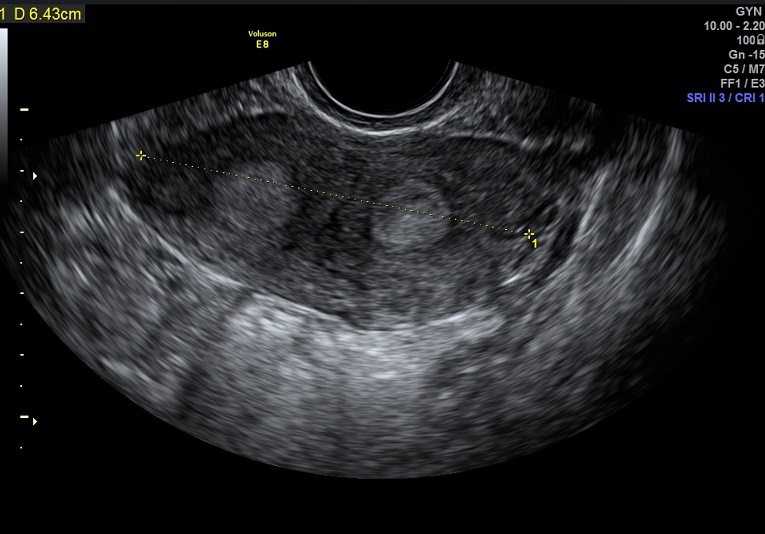

女性,25岁,原发性不孕2年,有子宫畸形病史,畸形类型不详。常规二维超声子宫横径增宽,宫底部横切面内膜不连续,动态扫查似显示为Y型。宫腔三维显示:两侧宫角分开成Y型,内膜凹陷达到宫颈内口。诊断:完全中隔子宫。